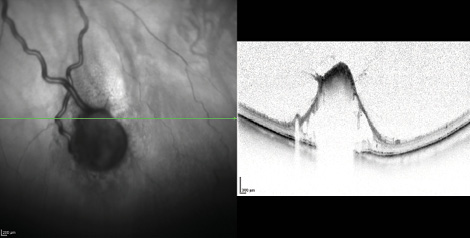

OCT showed no macular edema in any eye. Volume OCT scans, localized on the averaged periphery of the RCH, showed ectatic vessels. In Patient 3, slight perilesional edema and limited vitreous retinal traction were noted (Figure 4). Patient 6 showed the outcomes of argon laser treatment on the RCH (Table 2).

Figure 4. Patient 3: Vitreoretinal traction on RCH is shown on OCT.

When RCH is localized at the posterior pole or the midperipheral retina, volume OCT scans can assess the size of HBs and identify perilesional edema and vitreoretinal traction. If the RCH is in the extreme periphery, vascular leakage and lesion size can be assessed with FA (Figures 4 and 5). Retinal HBs that are small and peripheral normally will not cause significant visual symptoms; therefore, eye examinations can be repeated every 6 to 12 months. In patients with larger HB (such as Patient 6 in our study), or with macular edema or vitreoretinal traction the need for medical or surgical treatment should be assessed.